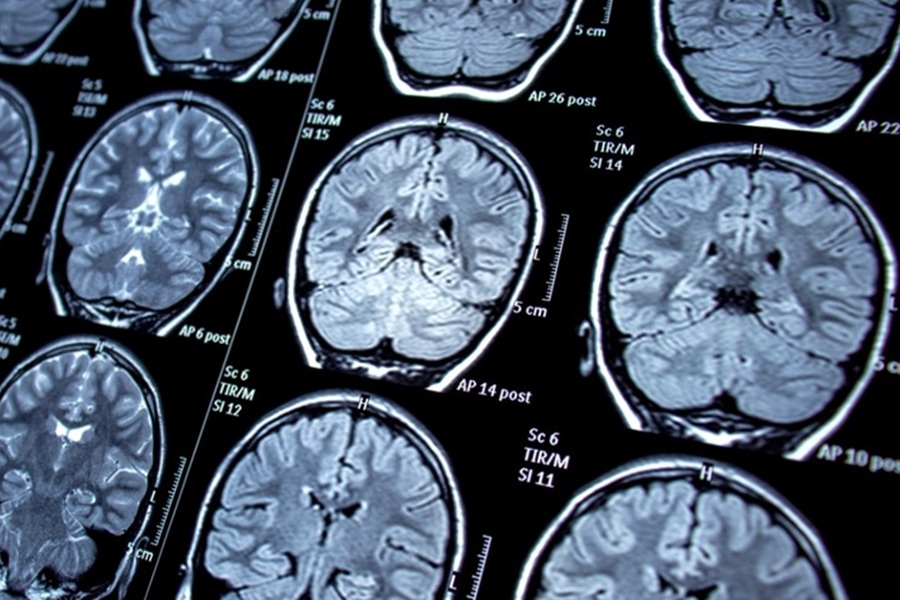

تشخیص تومور، به ویژه در نواحی حساسی مانند مغز، نخاع و ستون فقرات، لحظهای سرنوشتساز در زندگی هر فرد است که نیاز به اقدام فوری، دقیق و تخصصی دارد. در این مسیر پرچالش، اولین گام، تشخیص صحیح نوع و ماهیت تومور از طریق روشهای تصویربرداری پیشرفته و ارزیابیهای بالینی میباشد. پس از آن، انتخاب بهترین رویکرد درمانی که اغلب شامل مداخلههای جراحی پیچیده است، نقشی حیاتی در نتیجه نهایی ایفا میکند. دکتر القاسی، با تکیه بر دانش روز و تجربه گسترده در جراحی تومورهای سیستم عصبی، خدمات جامعی از تشخیص تا درمان را با هدف دستیابی به بهترین نتایج ممکن و حفظ کیفیت زندگی بیماران ارائه میدهد.

- انجام دقیق آزمایشها و تصویربرداریهای درخواستی: تصاویر بهروز MRI، CT اسکن و آزمایشهای خون، نقشه راه جراح هستند